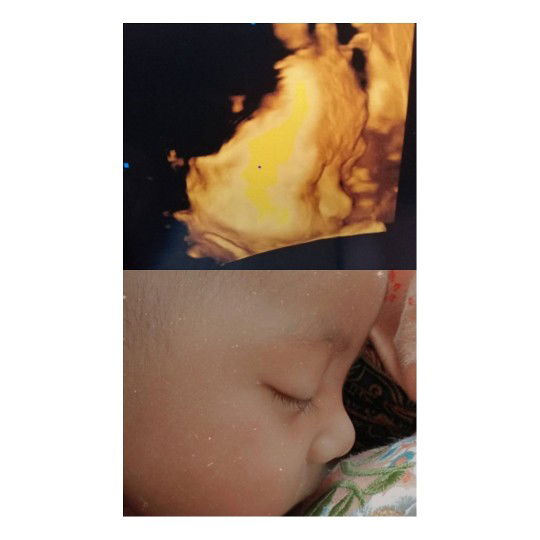

40week 1Day ,

Bun disini ada yg sm seperti sy tdk?sharing yu. Kemarin pas uk sy pas 40week sy ngflek lendir campur darah trus lungsung bagian bawah perut cenat cenut mules kek yg mau haid tp ini 5xLipatlah hhu , Tp belum intens bun . langsung cek ke bidan ternyata baru pembukaan 1 sy langsunt pulang lg karna gamau harus lama lamaan dibidan . sampe skrang belum ke bidan lagi karna kata bidan kl mules nya udah 5menit sekali atau mules nya udah gatahan atau cairannya udah keluar(ketuban) ksini lg . Tp belum ada basah basah sih bun cuman kl pipis keluar flek sm percis bnget ky yg sy litin di youtob (maafbunjorok) Apakah itu normal bun? sharing yu bun . Dan Mohon do'anya agar dede utun cepet keluar sehat sempurna ya bun